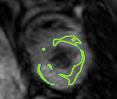

4.2 Visual assessment

We select the case that achieves the highest and lowest dice score for visual assessment. Fig. 4 shows example segmentation results where the proposed method achieved the highest agreement with the ground truth delineations. Fig. 5 shows example segmentation results where the proposed method achieved the lowest agreement with the ground truth delineations.